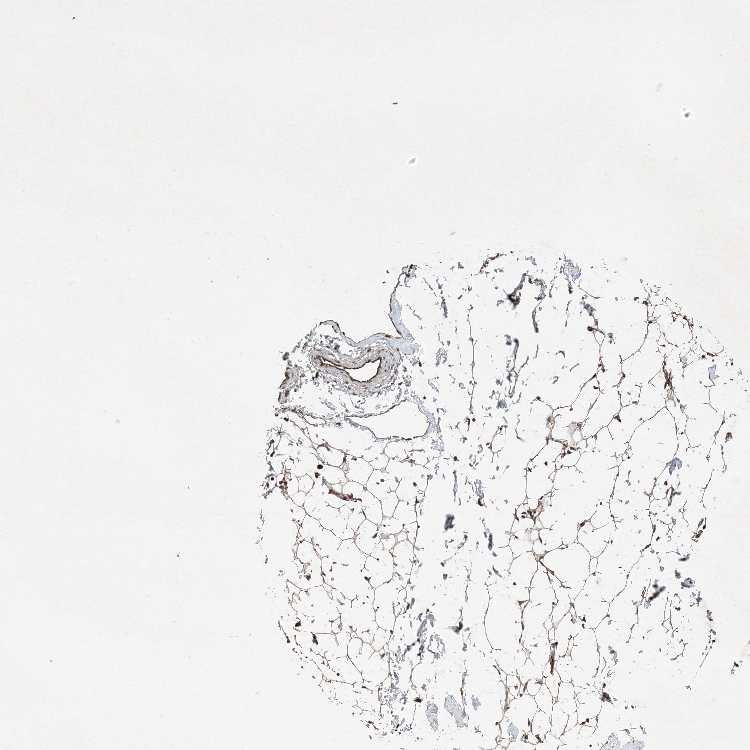

SOFT TISSUE 1 - Antibody stainingi

Antibody staining in the annotated cell types in the current human tissue is reported as not detected, low, medium, or high, based on conventional immunohistochemistry profiling in selected tissues. This score is based on the combination of the staining intensity and fraction of stained cells.

Each image is clickable and will lead to virtual microscopy that enables deeper exploration of all samples and also displays staining intensity scores, fraction scores and subcellular localization as well as patient and tissue information for each sample.

Antibody HPA034652Antibody HPA034653Antibody CAB034347

Fibroblasts LowHighMedium

Peripheral nerve MediumLowMedium